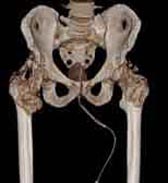

„CT“ ist die Abkürzung für Computer-Tomographie. Mit dieser Röntgen-Untersuchungsmethode können detaillierte Bilder vom Inneren Ihres Körpers erstellt werden. Die CT wird angewandt, wenn Ihr Arzt genauere Informationen benötigt, die herkömmliche Röntgenuntersuchungen nicht liefern können. Ein besonderer Vorteil der CT sind die kurzen Untersuchungszeiten auch bei großen Untersuchungsbereichen. Die Röntgenstrahlen werden in Ihrem Körper entsprechend der Dichte des Gewebes geschwächt, vom Detektor erfasst, elektronisch aufbereitet und im Computer in Grauwerte umgerechnet. Durch die sogenannte Fensterung lassen sich unterschiedliche Gewebearten (z. B. Lunge, Knochen, Weichteile) besonders detailreich darstellen. Mit mathematischen Verfahren können beliebige Schnitte und dreidimensionale Bilder berechnet werden.

Die CT ist ein Röntgendiagnoseverfahren, das im Gegensatz zu klassischen „Durchleuchtungen“ dreidimensionale digitale Informationen aus dem Körper liefert. Die Röhren-Detektoren-Einheit in der Gantry rotiert schrittweise oder permanent (Spiral-CT) um Ihren Körper, der auf dem Tisch vorgeschoben wird. Die Radiologie Darmstadt setzt einen Qualitätsstandard, indem alle CT-Untersuchungen mindestens an einem modernen 16-Zeilen-Mehrschicht CT-System durchgeführt werden; am Standort Alice-Hospital sogar an einem 256-Schichten FLASH-CT. Mit mathematischen Verfahren können beliebige Schnitte und dreidimensionale Bilder berechnet werden.